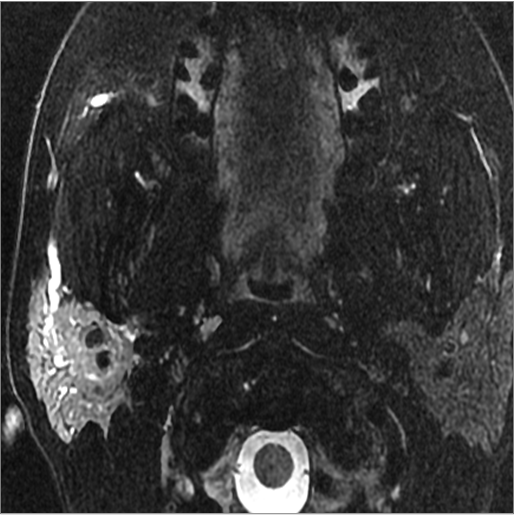

There is edema within the adjacent deep neck, retropharyngeal and/or prevertebral spaces [Yes/No]

There is abscess within the adjacent deep neck, retropharyngeal and/or prevertebral spaces. [Yes/No]

There is edema/abscess within in the prevertebral or paravertebral spaces. [Yes/No]

There is edema/abscess within in the epidural space. [Yes/No]